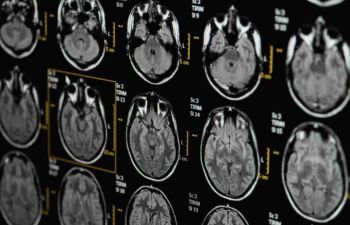

Head imaging

When assessing the need for head imaging, consider potential benefits and harms to avoid inappropriate imaging and to minimise the risk of harms.

Don’t perform imaging of the brain for non-acute primary headache disorders.